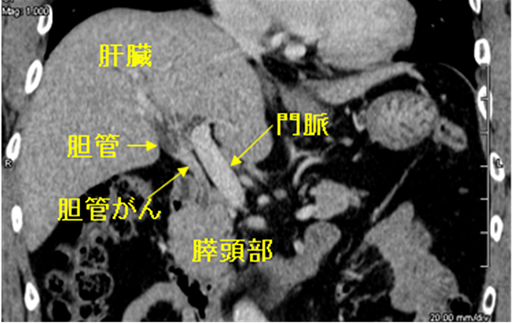

胆道および周囲臓器である肝臓、十二指腸、血管の解剖図を図1に示します。胆道とは肝臓で作られた「胆汁」という消化液を十二指腸まで運ぶ全経路を指し、胆汁を流す管である「胆管」、胆汁を一時的に貯留する袋である「胆嚢」、十二指腸の出口で胆汁の分泌を調整している「十二指腸乳頭部」に分けられます。細い胆管が肝臓の中を走行し、肝臓の中心に向かって徐々に合流して次第に太くなります。肝臓の外に出ると左と右の2本、さらにこの2本が合流して1本の管となります。途中で胆嚢へ分岐した後に十二指腸乳頭部につながります。肝臓の中の胆管を「肝内胆管」、肝臓の外の胆管を「肝外胆管」と呼びます。さらに肝外胆管は肝門部胆管、上部胆管、中部胆管、下部胆管の4つの部分に分けられています。下部胆管は膵臓の中を貫いて十二指腸につながっています。

がんは肝内胆管、肝外胆管のどちらにも発生しますが、肝内胆管がんは肝臓がんに分類されます。ここでは肝外胆管(胆管、胆嚢、十二指腸乳頭部)にできるがんに焦点を絞って説明します。胆道がんは胆管の内側の粘膜から発生します。直径がたった1cmしかない胆管は、がんがさほど大きくなくても簡単に詰まってしまいます。「胆管がんは小さいのであれば、治りやすいのではないか」と思われるかもしれません。しかし、胆管がんは主病変が小さくても、がん細胞が胆管外へ簡単に拡がり、進行しやすいといった特徴があります。なぜなら、胆管壁の厚さは非常に薄く、1mmもありませんので、胆管の内側にできたがんが外側に向かって進展すると、すぐに胆管壁を突き破り胆管の外に顔を出してしまうのです。図1を見ていただくと分かるように、胆管の近くには2種類の大事な血管が存在しています。この血管は肝臓に酸素を運ぶ「肝動脈」と小腸からの栄養分を運ぶ「門脈」で、胆管に接しながら並んで肝臓の中に入っていきます。さらに、胆管の周りには細かな神経やリンパ節も豊富に存在しています。このような解剖学的位置関係が原因で、がん細胞が胆管の外に出てくると、体全体につながる道筋である血管、神経、リンパ節へと簡単に浸入し全身に散らばるのです。これが胆管がんはたとえシコリとしては小さくても、広い範囲にがん細胞が広がっている事が多い理由です。この特徴が胆管がんを治しにくくしている元凶なのです。

X線で得られた情報をもとに体を輪切り状に画像化し、内臓の状態を詳しく知る事が出来る検査です。造影剤を注射することで臓器周辺の血管が白く映し出されるため、さらに詳細な情報を得る事が出来ます。最近のCTは0.5mm程度の間隔で輪切りにして撮影することが出来るようになったばかりか、画像をコンピューター処理することで、色々な方向で撮影した写真や立体的な画像を作ることができます。図2Aは通常のCTで得られるお腹の臓器の輪切り像ですが、図2Bのような縦切りの写真を作成すると、胆管が全長にわたって見えるようになるため、輪切りでは分かりにくかったがんの位置が分かるようになります。このように胆管がんに対して最新のCTで検査をすれば、胆管全体を詳しく観察することができますので、がんの存在部位を正しく診断することができます。さらに、胆管周囲の血管とがんの位置関係を詳細に観察することができますので、どんな治療が一番効果的なのか判定することができます。